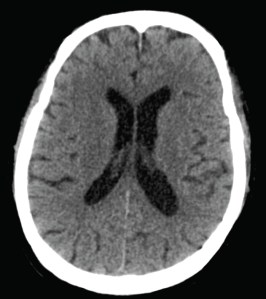

A middle-aged (late 50’s) housewife presented with fever for 4 days, associated with headache and photophobia. There was no significant contact or travel history, and her only chronic medical condition was hypertension for which she was on atenolol (a beta-blocker). Brought in to the emergency department by her husband and son, she was found to have a fever of 38.9 degrees Celsius, neck stiffness, and appeared mildly disoriented, answering questions appropriately but rather slowly. Her blood pressure was “normal” at 150/84 mmHg, and no neurological deficits were found on clinical examination. A CT head was done, which was normal (sample cut below).